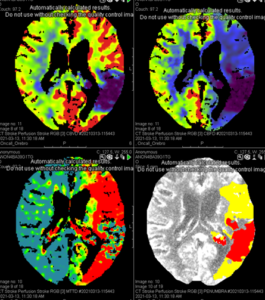

The next level in stroke diagnostics is the CT perfusion, adding information about how much of the brain is at risk if the clot isn´t removed and helping the neuro-interventionists with selecting the patients who would best benefit from an endovascular procedure for the mechanic removal of the thrombus (some patients are treated only medically, with thrombus-dissolving medications). The perfusion scan is obtained after injection of intravenous contrast agent; the CT scanner acquires images of the same area of the brain at different timepoints, measuring the inflow of contrast agent and thus adding a temporal dimension.

Perfusion scan showing established infarct (red, bottom right) vs area, which is ischaemic, but not yet infarcted, and thus salvable (yellow, bottom right)

The images from a CT perfusion scan must be post-processed; this can be done manually or using special software with an automated workflow. There are AI software capable of processing perfusion scans, an emerging and exciting field in Sweden right now!